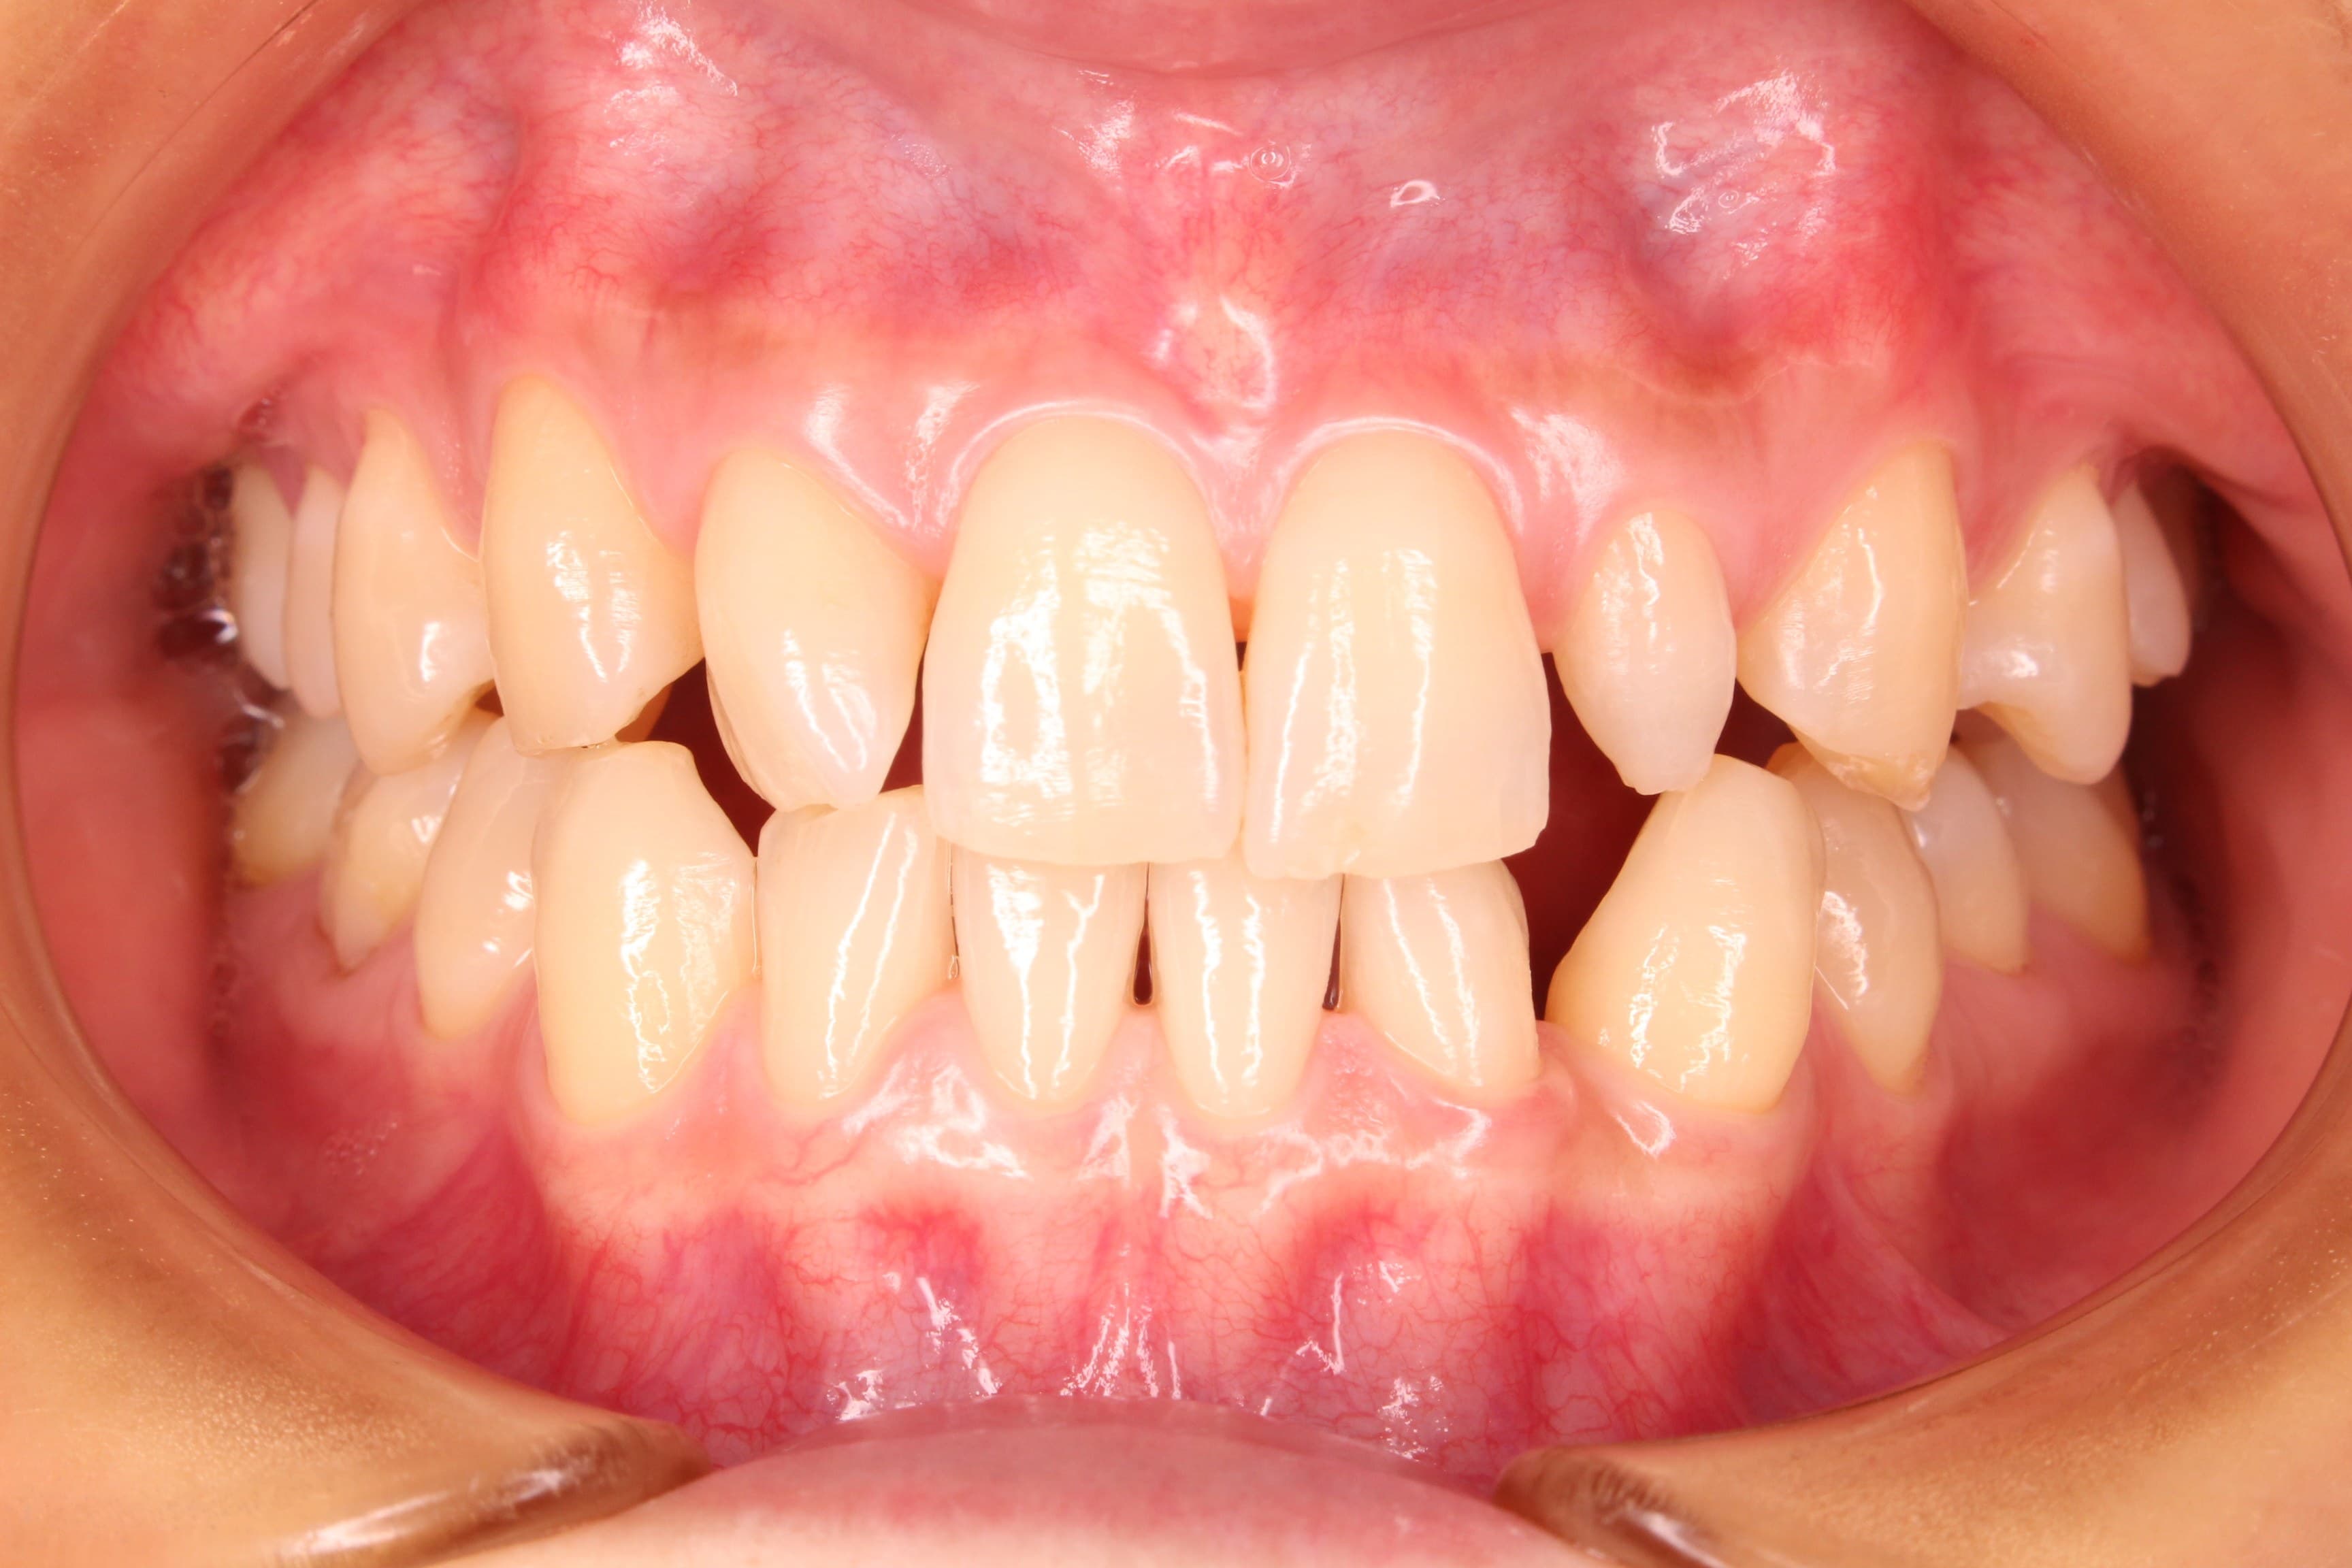

今回ご紹介する、歯周専門治療のケースは30代女性の方です。

20代の頃から、他院にて歯周病と診断され、頻繁に痛みを伴う腫れと出血を繰り返していました。

その度に消毒と抗生物質で抑えていたそうです。その時は治るけど、暫くするとまた繰り返して段々と歯茎が下がってきた・・・。

このままだと、どんどん下がってしまうのではないかと、不安になり来院されました。

治療の途中から、ご本人でも状態の改善が自覚でき、腫れや出血の心配が無くなったと、とても安心されていました。

私達も、症状が改善された事はもちろん、○○さんの不安が解消されて、とても安心しています。